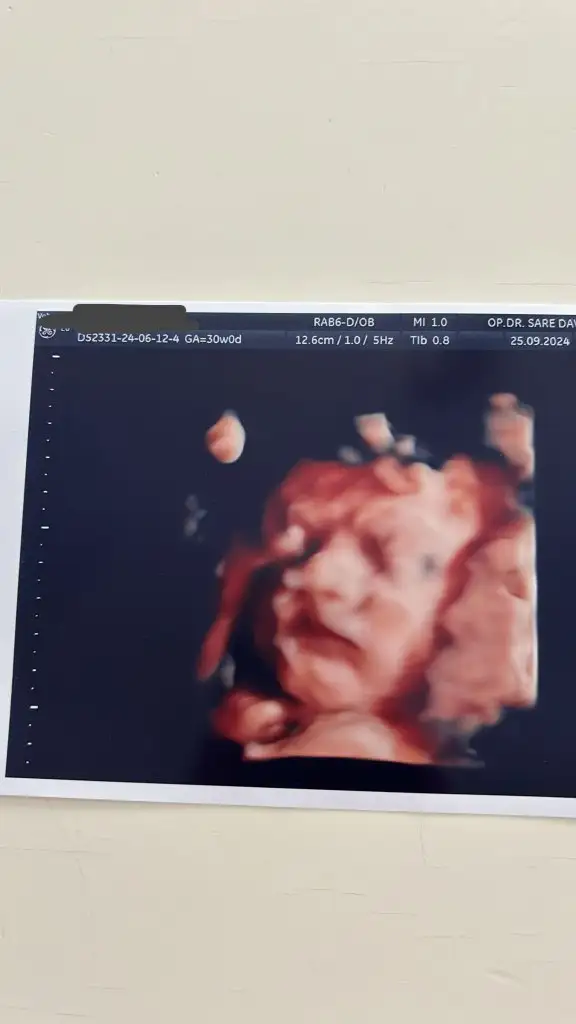

bugün 30+0 ım doktor kontrolum vardı. Benim bebik 1800 40 cm olmuş. Yine onden gttiği için dikkat et kilo ekmek tatlı patates pilav ölcülü ye aldırma bebege fazla dedi oyle actım ki geldiğimde normalde yemem inat gibi ekmege abandım kahvaltıda tövbe estagfir😀 bebek hala dönmemiş bir pozisyon gösterdi doktor onu yapcakmışım akşamları su iki hafta bir sonraki kontrole kadar dönmesi için . İnş işe yarar ya.

Bir de benim tosbikusun fotosuu, asabi bir bey 😂😂

benimki de makat gelis yine ne gibi hareket onerdiler? Donmese de olur sezaryan dogum icin aslinda, benim bir de dusuk plesanta yine normal dogum sansim hic yok. ne kadar net gozukuyor bebegin ultrason resmi. Benimki de bu 🙂